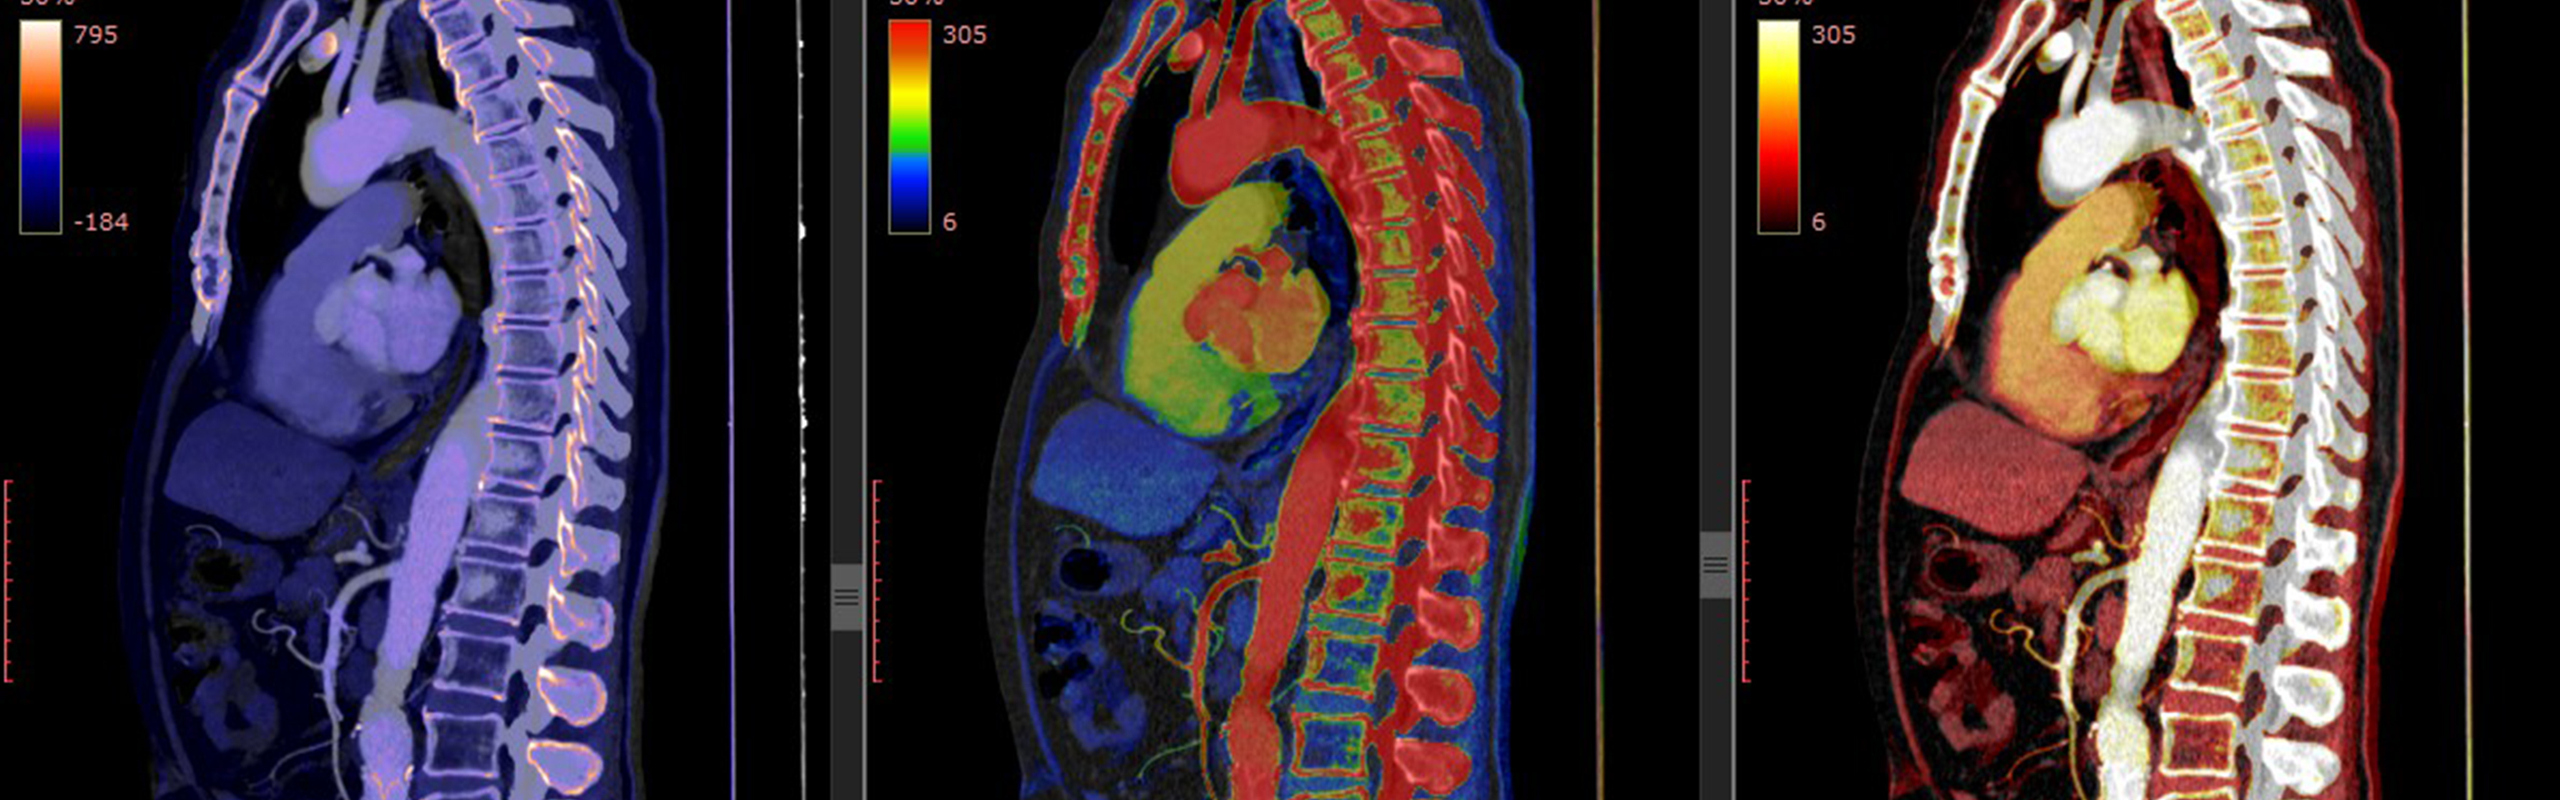

Datortomografi av thorax och buk.

Radiologi är en bild- och funktionsmedicinsk specialitet där avancerade avbildningstekniker som röntgen, datortomografi (DT) och magnetresonanstomografi (MR) används. Radiologisk diagnostik möjliggör upptäckt av inre sjukdomar och skador samt monitorering av behandlingseffekter. Specialiteten integreras också i många nuklearmedicinska undersökningar samt vid interventionella procedurer, där läkare använder bildvägledning för minimalinvasiva ingrepp.

Specialiteten radiologi innefattar kunskaper och färdigheter i bildgivande diagnostiska metoder baserade på joniserande röntgenstrålning, magnetresonans och ultraljud. Inom grenspecialiteten nuklearmedicin används radioaktiva isotoper som sönderfaller med gammastrålning.

Verksamheten vid Bild- och funktionsmedicin, Norrlands Universitetssjukhus, omfattar i dagsläget bilddiagnostiska metoder som konventionell röntgen och genomlysning, datortomografi (DT), ultraljud, magnetresonanstomografi (MR) samt nuklearmedicinska undersökningar.